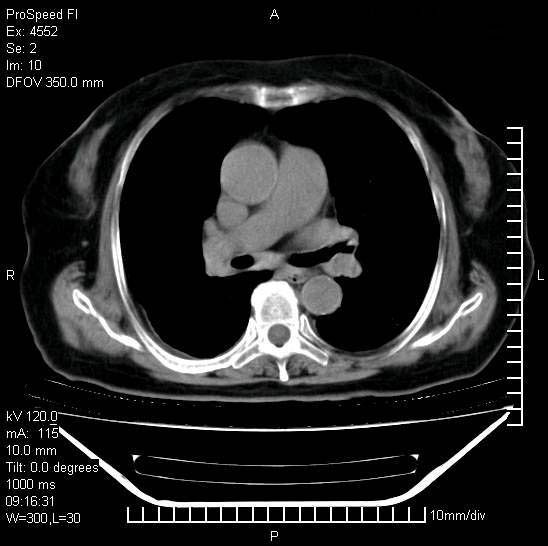

今天ct

短短几天内,病变范围明显增多扩大,以左侧明显,而且双侧出现胸水,还是考虑感染.

短短几天内,病变范围明显增多扩大,以左侧明显,而且双侧出现胸水,我更多考虑左侧中心性肺癌并并阻塞性不张及肺炎,炎症变化也太快了!

1)两肺结核并感染。2)不排除左肺上叶中央型肺癌并阻塞性肺炎、肺不张可能;建议行纤支镜检查。3)右肺门及纵隔淋巴结肿大。4)双侧胸腔积液。